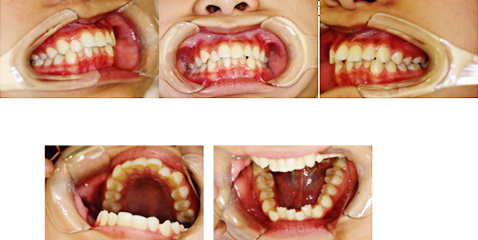

正畸治疗还要把握时机,有一些牙颌畸形如“地包天”、咬唇、吮指等不良习惯引起的畸形,要在三到五岁就进行治疗,越早治疗越好。一般的牙颌畸形在恒牙已经开始萌出时,也就是八到十岁时侯到正畸医生处做咨询、检查以便决定。青春快速生长发育期(一般女孩11~13岁,男孩12~14)时,牙齿替换完毕,颌骨仍有发育潜力,此时是进行固定矫治的最佳时期,绝大多数错颌畸形均可在此时解决。矫正之前医生会进行详细的口腔检查,拍X光,取分析模型,进行全面的综合分析,再得出正确的诊断和治疗计划,一般需要治疗一至两年,然后转入保持期。一些严重的骨性错颌,矫正后可能达不到理想的效果或因异常的生长型导致复发,需在成年后进行正颌外科手术矫正。

根据矫治器的不同,儿童正畸的常规方法可以分以下几类:

1、活动矫治器

对于处于乳牙和替牙期的爱美者,这是最佳的牙齿矫正的方法,比较简单。也可用来配合固定矫治器进行矫治,爱美者可以自己摘戴,比较方便。

2、固定轿治器

这是主要用于替牙期或者刚刚换好牙,身体还处在生长发育高峰的儿童。这是最为常用的矫治器,却不能自由摘戴。

3、功能轿治器

主要用于替牙期或者刚刚换完牙还处于生长发育高峰期的儿童,利用功能矫治器可以矫正骨性错和畸形。

无托槽隐形矫治器

很多爱美者因为工作等原因,对形象要求较高,所以最适合采用无托槽隐形矫治器,爱美者可以自行摘戴。不过,这种方式只适合轻度的牙列拥挤和个别牙的扭转。